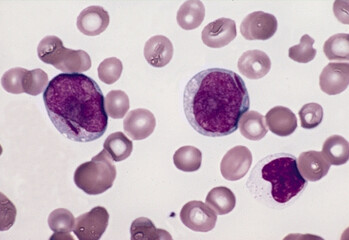

Annexin A3 as a Diagnostic Biomarker and Therapeutic Target for Treating Hepatocellular Carcinoma

Therapeutic Biologics

PD1-Based TWIST1 Cancer Vaccine